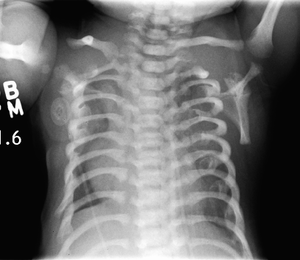

CXR of a newborn with asphyxiating thoracic dysplasia. Note the short ribs.